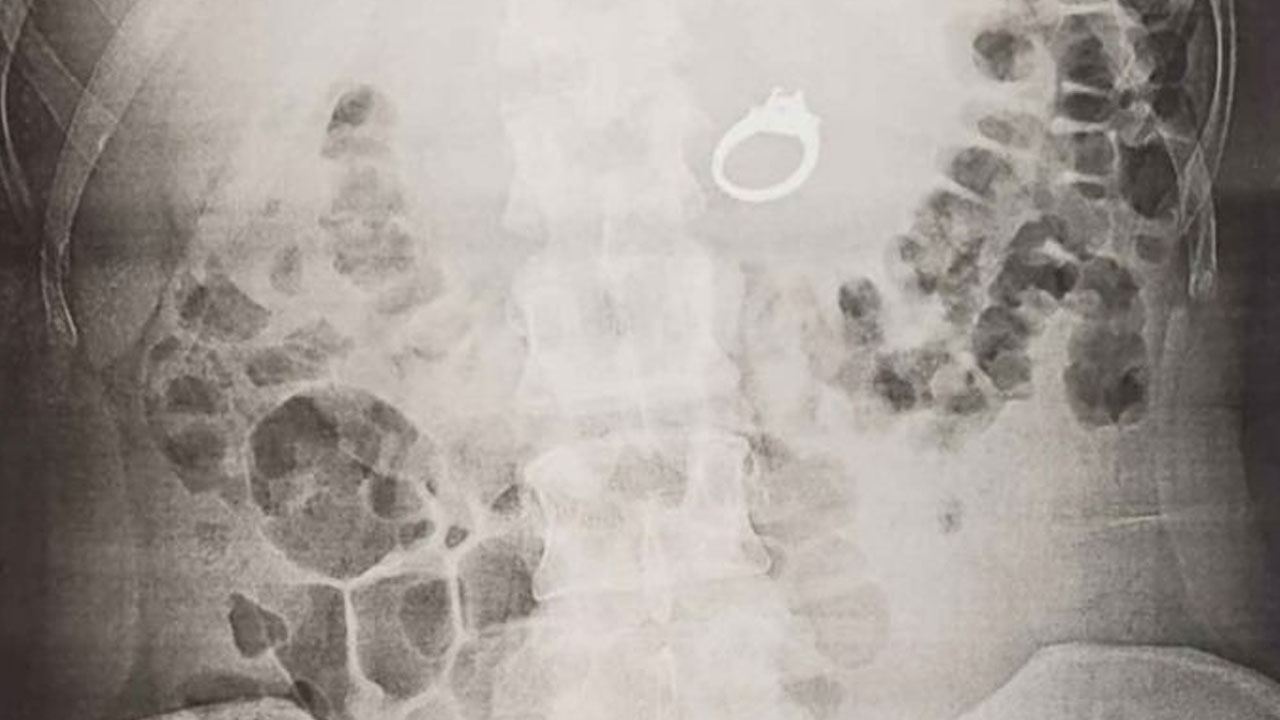

En el sueño la única opción para salvarlo era tragárselo. Al despertarse, se sintió aliviada de que solo fuera una pesadilla, hasta que notó que el anillo ya no estaba en su dedo.

Al darse cuenta de que, efectivamente, lo más probable era que se hubiese tragado la alianza, despertó a su novio para contarle lo ocurrido. Según lo relató Jenna en una publicación de Facebook, los dos se rieron “durante aproximadamente una hora y media”, después acudieron a un centro médico.

De acuerdo con información de CBS, los especialistas descartaron la opción de esperar a que el anillo saliera por vía natural y remitieron a la paciente al servicio de gastroenterología, donde le practicaron una endoscopia superior y recuperaron el anillo.